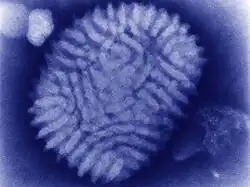

| Myxoma virus (transmission electron microscope) | |

Myxoma virus is in the genus Leporipoxvirus (family Poxviridae; subfamily Chordopoxvirinae). Like other poxviruses, myxoma viruses are large DNA viruses with linear double-stranded DNA. Virus replication occurs in the cytoplasm of the cell. The natural hosts are tapeti (Sylvilagus brasiliensis) in South and Central America, and brush rabbits (Sylvilagus bachmani) in North America. The myxoma virus causes only a mild disease in these species, with signs limited to the formation of skin nodules.[3]